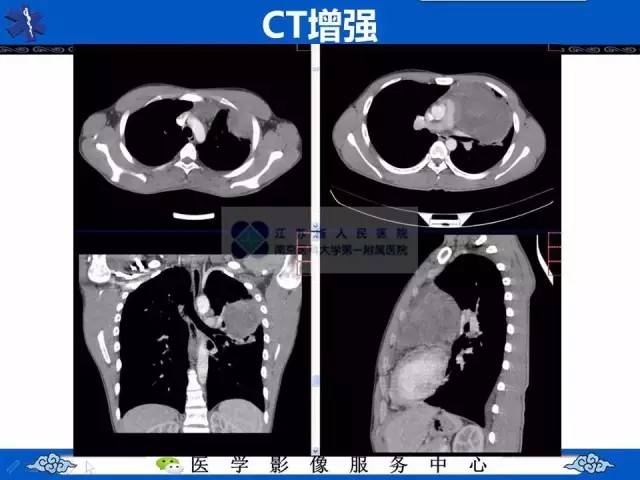

【病例】纵隔内胚窦瘤1例CT影像表现